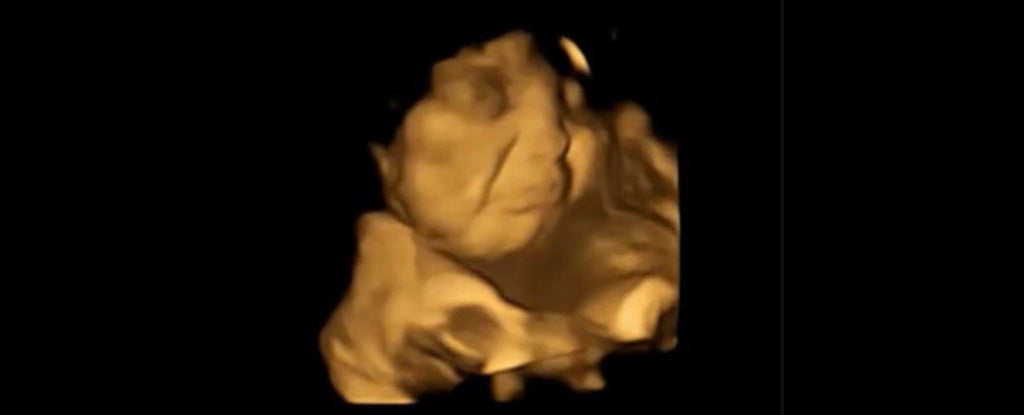

Según el estudio, el sabor de la col rizada es tan repulsivo para los fetos que hace que arruguen la cara con disgusto mientras están en el útero, tal y como revelan las imágenes. Para ello, los investigadores utilizaron ultrasonidos 4D con los que observar las reacciones de 100 bebés a los sabores ingeridos por sus madres, descubriendo que responden favorablemente a ciertos alimentos, y que no les gustan las verduras de hoja verde.

Cuenta el equipo que los hallazgos son la primera evidencia directa de que los bebés reaccionan de manera diferente a varios olores y sabores antes de nacer. Para ello, examinaron ecografías 4D de 100 mujeres embarazadas y descubrieron que los bebés expuestos a sabores de zanahoria mostraban respuestas de “cara de risa”. Por contra, aquellos expuestos a sabores de col rizada mostraron más respuestas de “llanto”.